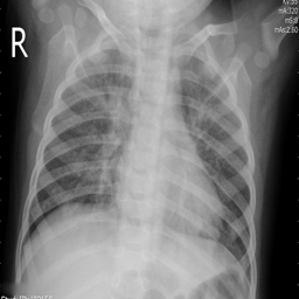

Research is based on the second update of the "COVID-19 Radiography Database" Chowdhury et al. (2020); Rahman et al. (2021); Cov (2022) developed by a team of researchers from Qatar University, Doha, Qatar, and the University of Dhaka, Bangladesh along with their collaborators from Pakistan and Malaysia in collaboration with medical doctors. The database incorporates posterior-to-anterior (AP)/anterior-to-posterior (PA) chest X-ray images from multiple public sources Vayá et al. (2020); Winther et al. (2020); SIR (2020); Cohen et al. (2020a, b); Haghanifar et al. (2022); RSN (2018); Kermany et al. (2018) and contains: 3616 images of COVID-19-positive cases, 6012 images of lung opacity (non-COVID lung infection), 1345 images of viral pneumonia, 10192 images of healthy lungs. Images are provided after conversion to common PNG format with 256x256 dimensions. For each image, the dataset authors provided a corresponding lung segmentation mask obtained using a dedicated U-Net model Rahman et al. (2021). Sample images from the database are presented in Fig. 2.

Images in the original dataset are not framed consistently, with body parts visible in the image tending to differ depending on the original source. In order to remove this possible bias all images are cropped to a rectangular region of interest encompassing the corresponding lung mask. After cropping the images are resized to a common size of 128x128 pixels. An example of cropped and rescaled image is presented in Figs. 2f and 2g. Finally, the pixel values are normalised to [0; 1] scale. All images are grayscale with three channels present, such format is retained as an input for the classification networks as this is the format they were trained on originally. For the GAN training, a single-channel grayscale format is used which leads to faster execution.

Many images in the dataset contain annotations or marks made during the image acquisition or afterwards by a radiologist. Examples of such images are presented in Fig. 3. Such symbols in the training dataset are known to generate biases as classifiers tend to target their attention to the presence of the symbols instead of genuine features of the image Rajaraman and Antani (2020); DeGrave et al. (2021). Therefore after the initial preprocessing, consisting of cropping and resizing all images containing such elements were removed.